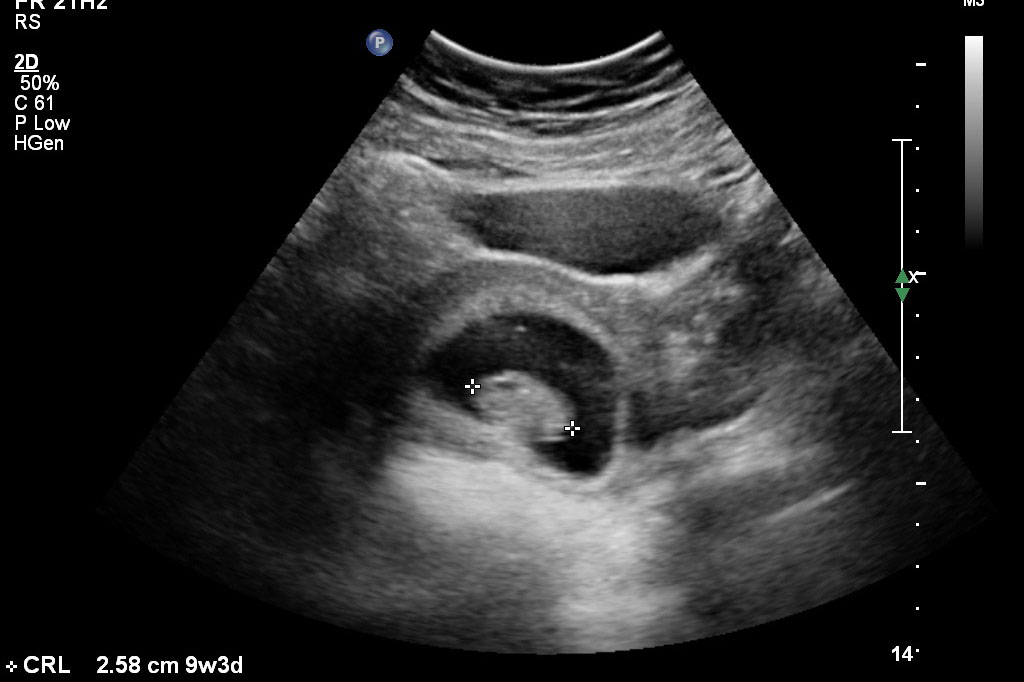

This time, we were able to concentrate on Beanie and he/she is doing great! From what we can tell, everything looks right on target. Strong, regular heartbeat (163) and measuring perfectly on schedule.

So without further delay... Beanie at 9 weeks!

You can see Andie's small little sack fading away to the right of Beanie's.